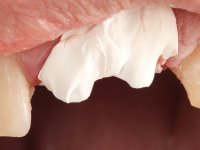

Foi feito o tratamento endodôntico dos dentes 2.1 e 2.2.de imediato, a sintomatologia que o paciente manifestava a isso impunha. Na mesma consulta foi realizada uma extensa gengivetomia com o bisturi elétrico, no sentido de expor os limites cervicais da fratura. Foram colocadas resinas compostas nos remanescentes radiculares com a intenção de reformular a emergência dos tecidos moles. Realizei a impressão dos remanescentes radiculares para confeção em laboratório de uma ponte provisória. A ponte provisória de 2 elementos, apresentava um formato que visava no futuro acomodar o coto dos espigões falsos cotos que iria ser cimentados nos remanescentes radiculares. Apresentava um reforço metálico palatino e dois apoios para os dentes adjacentes, um mesial e outro distal. Os remanescentes radiculares foram preparados para a confeção de dois espigões falso coto fundidos. As linhas de acabamento cervical foram definidas e os canais radiculares desobturados e preparados. A impressão foi realizada com a utilização de tutores de plástico com a técnica de dupla mistura. O afastamento gengival foi feito utilizando pasta de caolino. A ponte provisória foi rebasada em boca com acrílico auto polimerizavel, cimentada provisoriamente sobre as raízes e os apoios colados aos dentes adjacentes. No laboratório foram confecionados os E.F.C. fundidos, tendo o cuidado de preservar espaço para a definição no re preparo dentário da linha de acabamento cervical. Removida a ponte provisória foi feita a cimentação dos E.F.C. fundidos com cimento de ionómero de vidro reforçado com resina. A ponte provisória teve que ser retocada para permitir a acomodação dos cotos e simultaneamente foi readaptada à redefinida linha de acabamento cervical. Durante 2 meses a ponte provisória acompanhou a estabilização periodontal das raízes traumatizadas e simultaneamente conseguiu a maturação da arquitetura gengival.